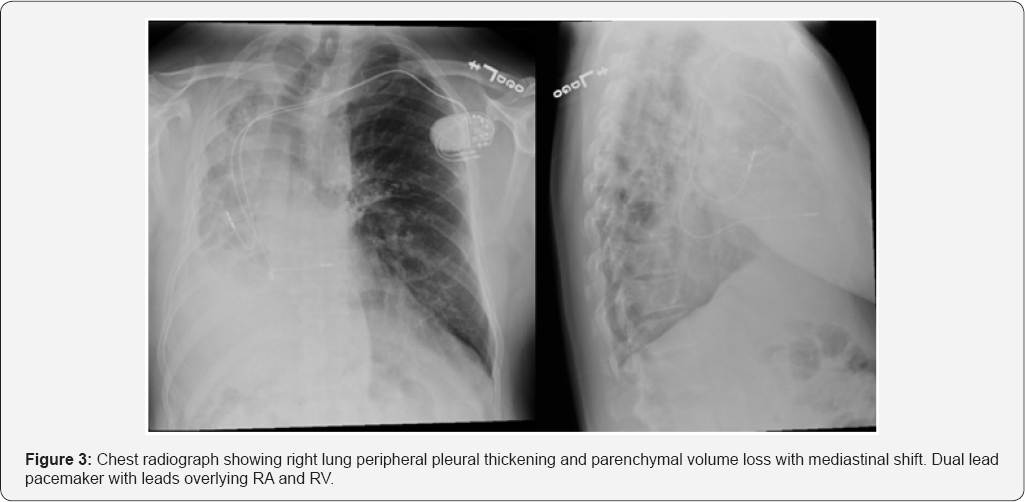

The patient was taken to the cardiac cath lab for implantation of a permanent pacemaker. Right ventricular (RV) lead placement was as follows: venous access was through cephalic vein dissection. Fluoroscopy images showed that the patient's heart was displaced to the right, which made it impossible to advance the RV lead into the right ventricle despite multiple attempts with different manually curved stylets. 9Fr coronary sinus (CS) delivery system (Biotronik -Selectra Extended Hook 45cm, model number 375527) was used to get into the RV over Terumo glide wire. The ventricular lead was next introduced through the 9Fr long CS sheath and positioned into the right ventricular lower septum. Following this procedure, the permanent pacemaker was successfully placed (Figure 3).

A 55-year-old male, from the Dominican Republic, with a history of treated pulmonary tuberculosis of the right lung, presents to the primary care clinic with a history of several months of palpitations, unrelated to physical activity. Chest imaging showed right lung peripheral pleural thickening and parenchymal volume loss with mediastinal shift to the right. Subsequent Pulmonary Function Tests: showed severe airway obstruction, without response to bronchodilators and severely decreased total lung capacity and diffusing capacity. EKG: sinus rhythm. The patient was then diagnosed with the Post-pneumonectomy-like syndrome.